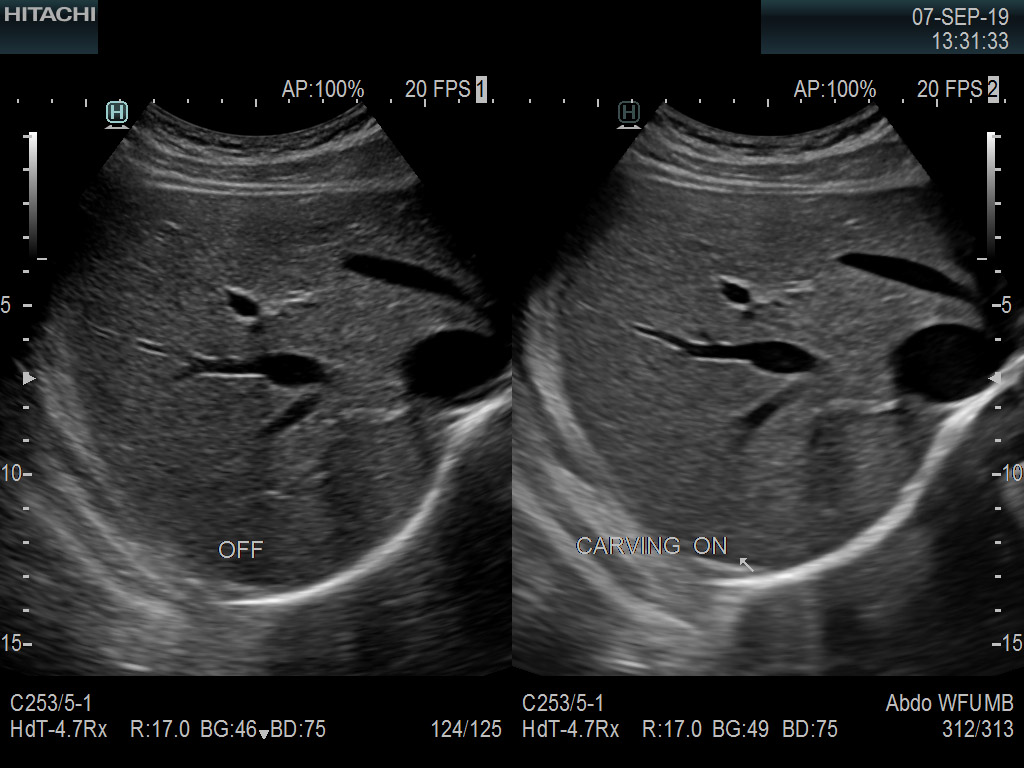

Recognized for our outstanding image quality, outstanding system reliability and intuitive use of cutting edge technology, Fujifilm Healthcare remains the standard in the field of Surgery.

Fujifilm Healthcare’s ARIETTA Precision features state-of-the-art digital architecture and advanced imaging technologies to redefine the capabilities of surgical ultrasound.

Imaging Clearly Defined

State-of-the-art digital architecture and advanced imaging features to redefine the capabilities of surgical ultrasound.